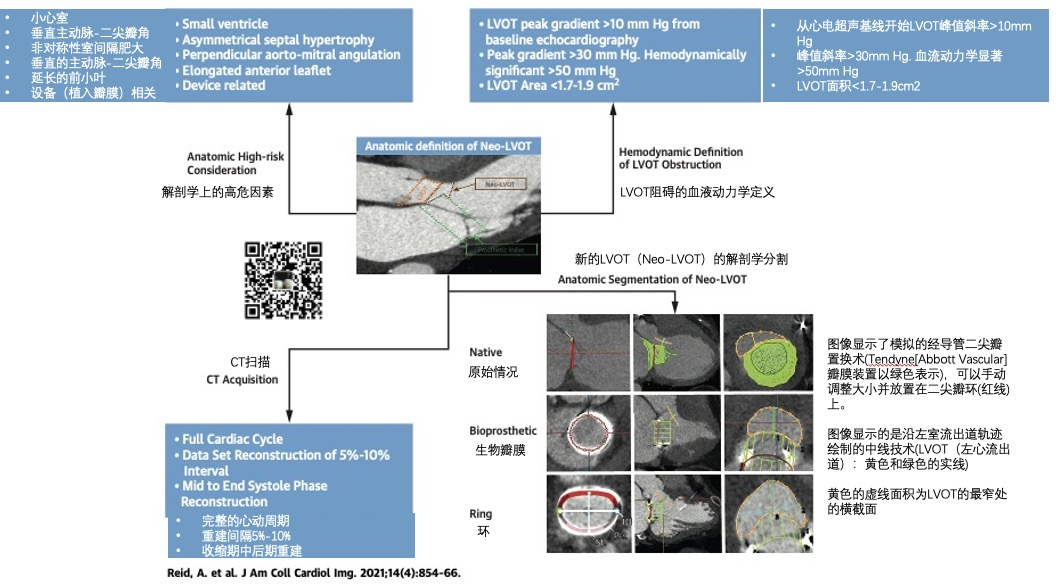

如下图所示,心脏CT图像可以在术前心脏CT扫描上生成模拟的新左室流出道(Ref 43)。

新的左心室流出道已被迅速采用为预测植入后左室流出道压差风险的关键解剖学指标,并用于瓣膜植入前的筛查。

Reid A , Ben ZekryS , Turaga M, et al . Neo-LVOT and Transcatheter Mitral Valve Replacement: Expert Recommendations. JACC Cardiovasc Imaging 2021;14(4):854–866. -